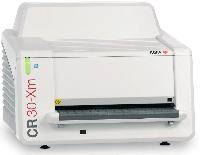

Мобильный рентгенаппарат + оцифровщик. Получение рентгеновского изображения на экране ноутбука. Вариант за 1,4 миллиона рублей под ключ.